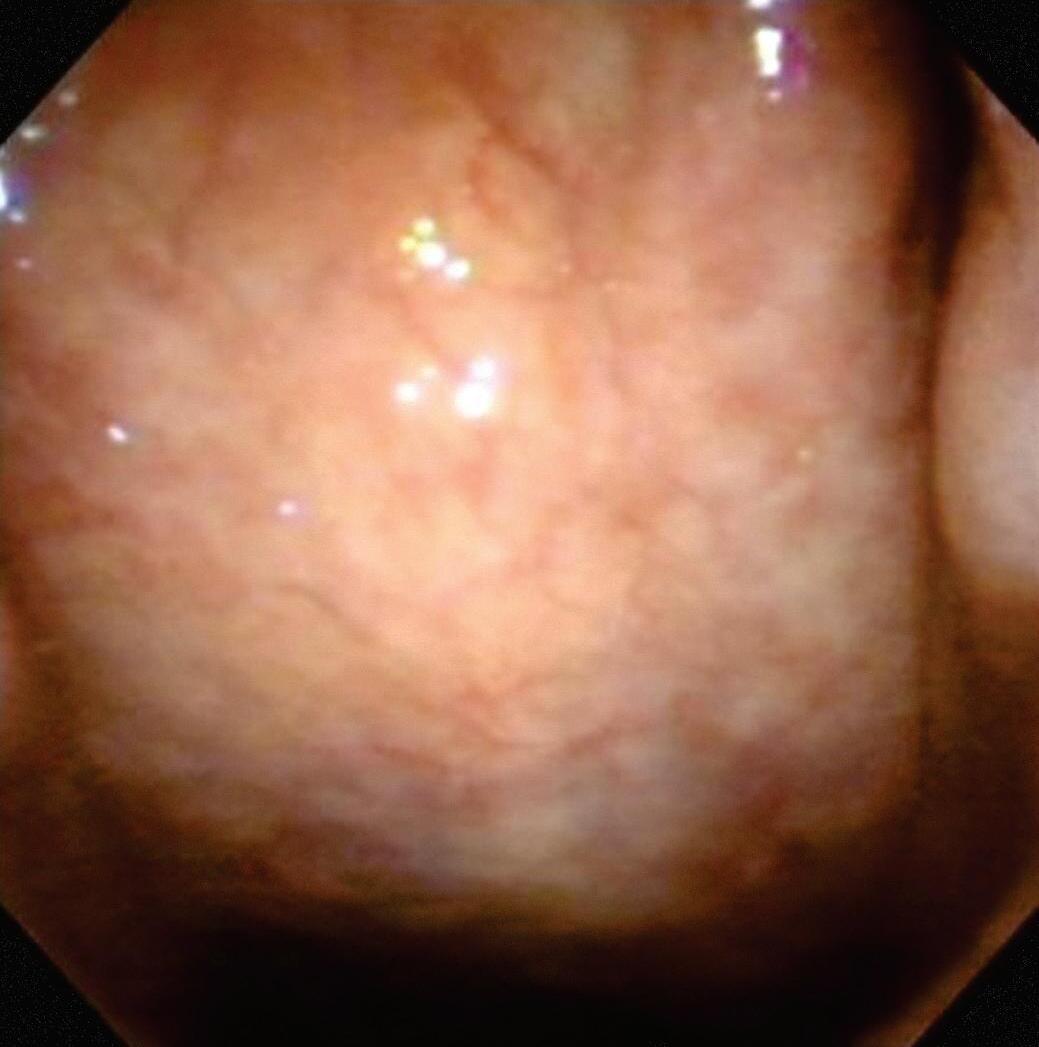

A Figura 1.1 mostra os níveis de saburra lingual, conforme classificação de Maracchio e Conceição (2009).

Figura 1.1 (A a E) Grau de saburra lingual. Grau 1 – saburra leve no terço posterior da língua (A). Grau 2 – saburra leve nos terços posterior e médio da língua (B). Grau 3 – saburra moderada no terço posterior da língua (C). Grau 4 – saburra moderada nos terços posterior e médio da língua (D). Grau 5 – saburra moderada nos terços posterior, médio e anterior da língua (E) Fonte: imagens pertencentes aos autores.